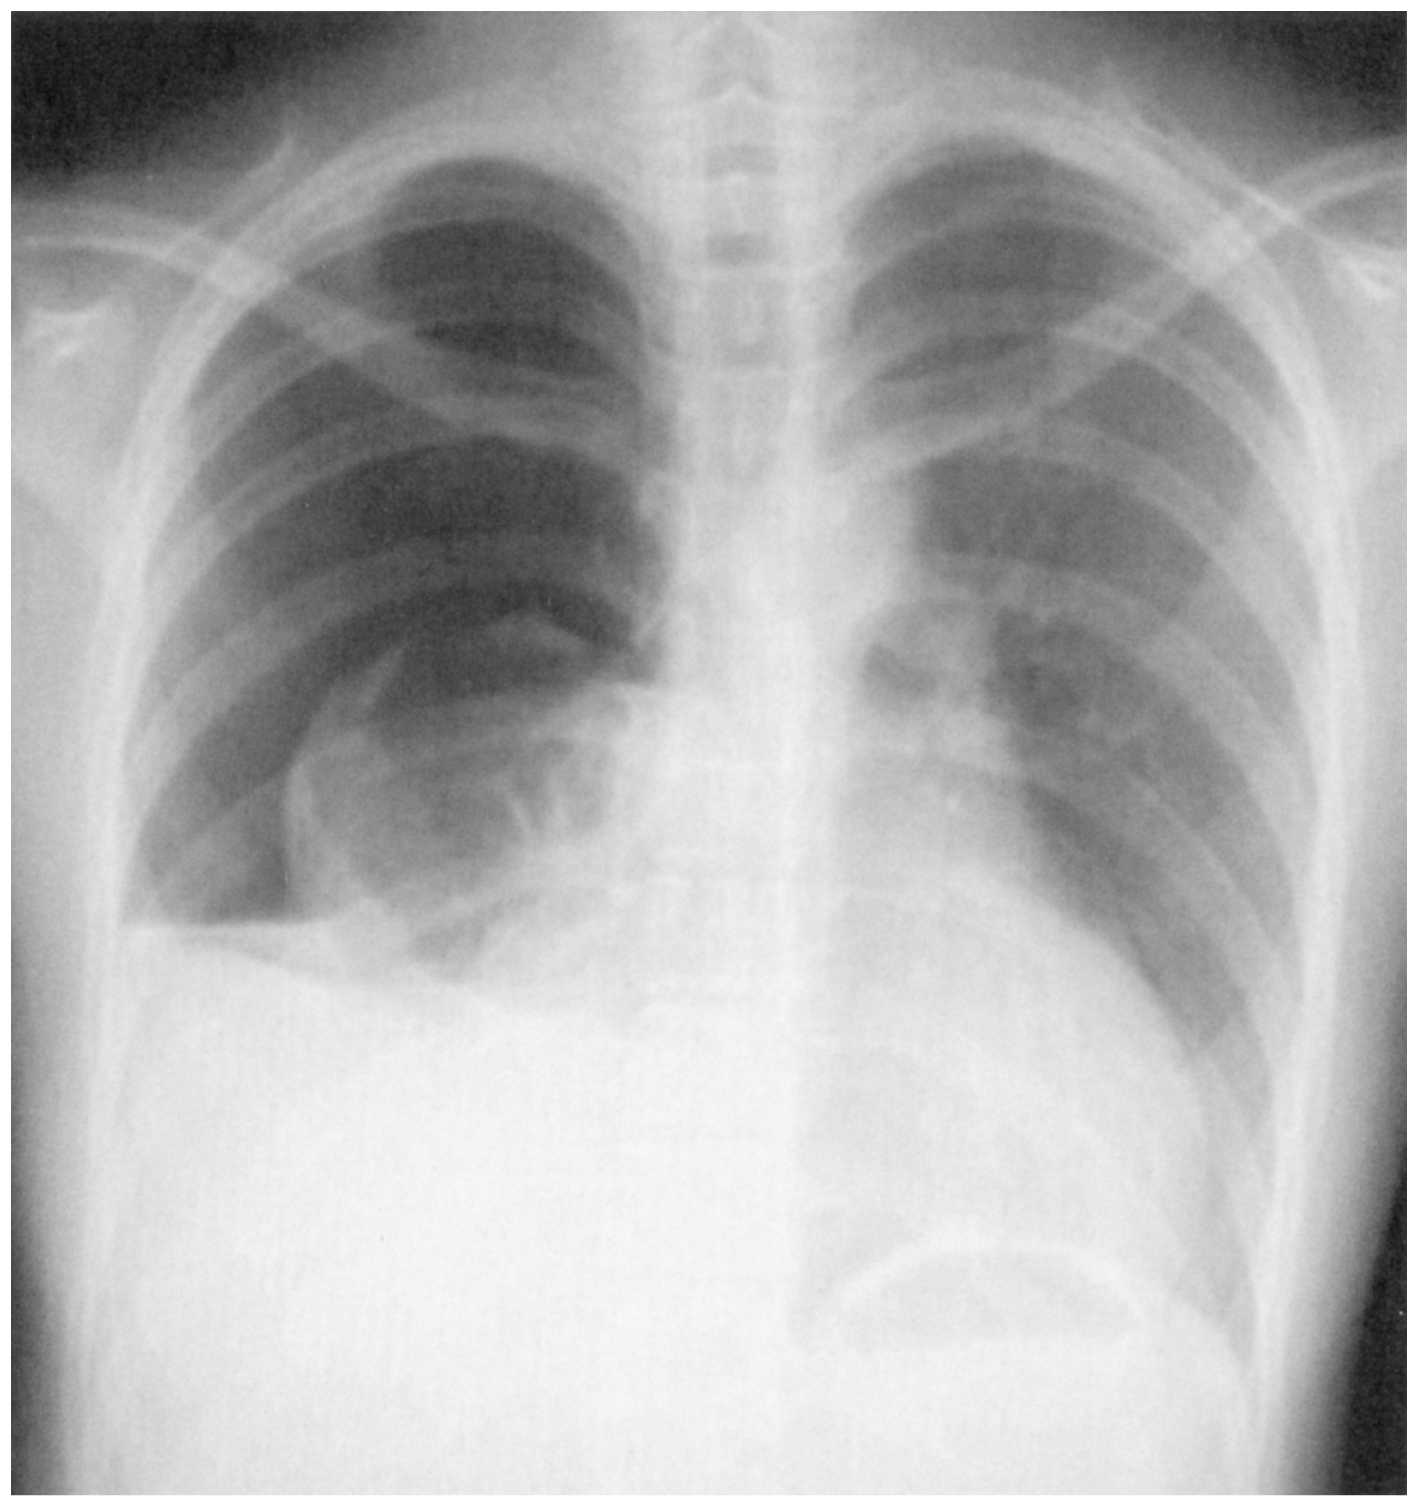

20歳の女性。胸痛と息苦しさとを主訴に救急車で搬入された。1時間前,咳をした後に右胸痛と呼吸困難が出現し,次第に増悪したため救急車を要請した。身長162cm,体重48kg。体温36.5℃。心拍数108/分,整。血圧84/48mmHg。呼吸数18/分。SpO2 95%(リザーバー付マスク10L/分 酸素投与下)。眼瞼結膜は貧血様である。心音に異常を認めない。呼吸音は右で減弱している。血液所見:赤血球290万,Hb 9.5g/dL,Ht 29%,白血球10,690,血小板19万。胸部エックス線写真を下に示す。輸液を開始し胸腔ドレナージを施行したところ,血性排液1,200mLがあり持続的に空気漏れがみられた。ドレナージ2時間後,胸腔ドレナージ排液は血性で1時間200mLの排液と空気漏れが持続しており,SpO2 99%(マスク8L/分 酸素投与下)であった。この時点で末梢血液所見は赤血球245万,Hb 7.5g/dL,Ht 24%,白血球12,600,血小板18万であった。心拍数120/分,整。血圧70/40mmHgで赤血球輸血を開始した。

無料会員登録していただくと、実際の解説をすべて見ることができます。急性の呼吸困難を主訴とする疾患としては,喉頭浮腫,気道異物,自然気胸,気管支喘息,慢性閉塞性肺疾患の急性増悪などの呼吸器疾患,心不全(急性,慢性の急性増悪),肺血栓塞栓症などの循環器疾患が代表的である。この症例では呼吸器感染症と心不全が疑われるが,胸部エックス線写真は肺炎像というよりも両心不全を示唆する所見を示している。診断:心不全(両心不全)(Nohria分類wet and warm) 選択肢考察 ×a 強い呼吸困難,胸痛などにより安静が保てない場合には,血管拡張による前負荷軽減と,交感神経抑制による心筋酸素消費量の減少を目的としてモルヒネを使用する。この症例ではモルヒネが必要となるほどの興奮状態ではない。